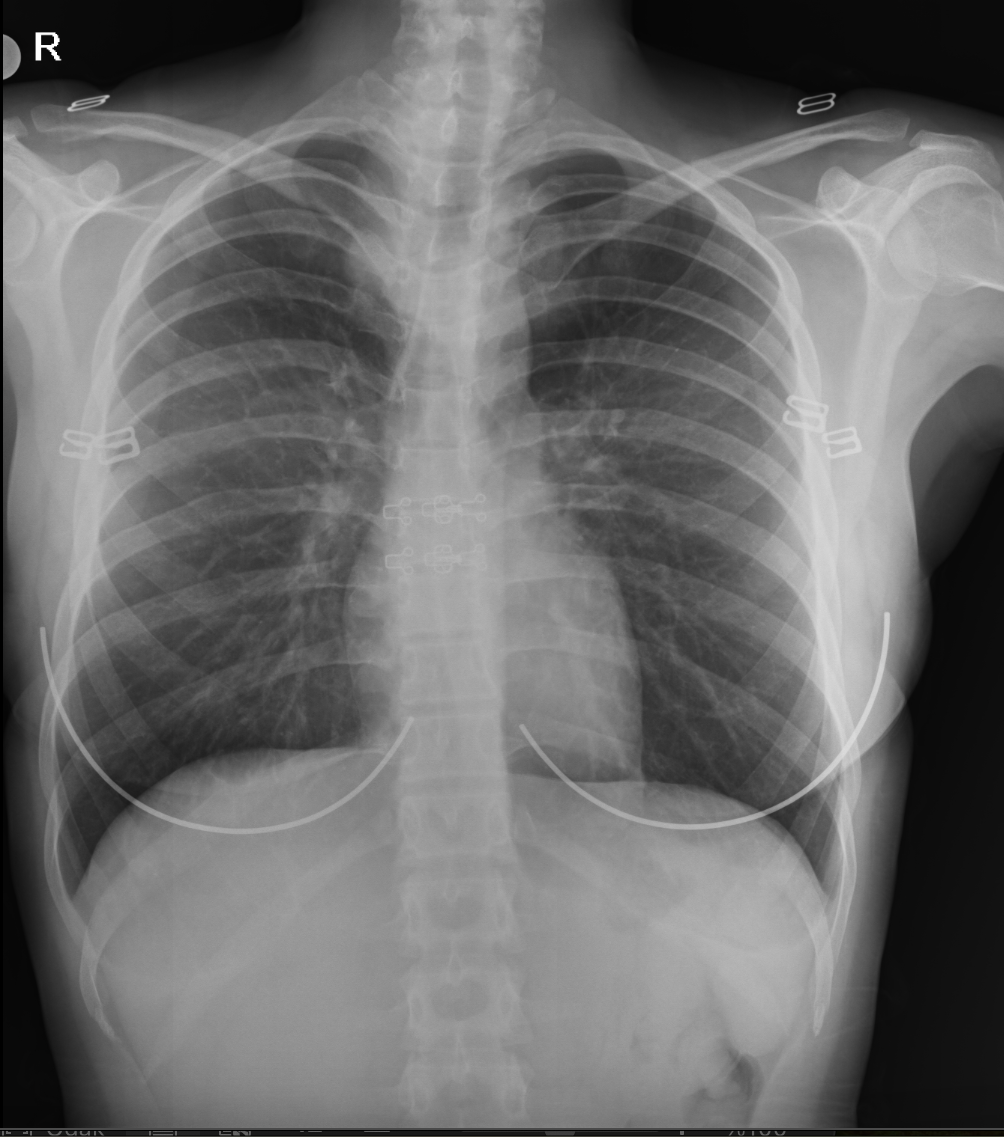

Postroanterior akciğer grafisi 1 yıl önceki akciğer grafisi ile karşılaştırıldığında sağ üst mediastende genişleme görüldü (resim 2)

| 17.11.2023 | 21.11.2024 |

Resim 2: 2024 yılında çekilen akciğer grafisinde 1 yıl önce çekilen grafide görülmeyen sağ üst mediastende genişleme.